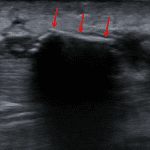

Indication: Puncture wound

- Mid pretibial soft tissue edema without subcutaneous gas or radiopaque foreign body. Consider ultrasound for further evaluation if there is clinical concern for retained foreign body

- Radiolucent foreign body (wood)

Mid pretibial soft tissue edema without subcutaneous gas or radiopaque foreign body. Consider ultrasound for further evaluation if there is clinical concern for retained foreign body.